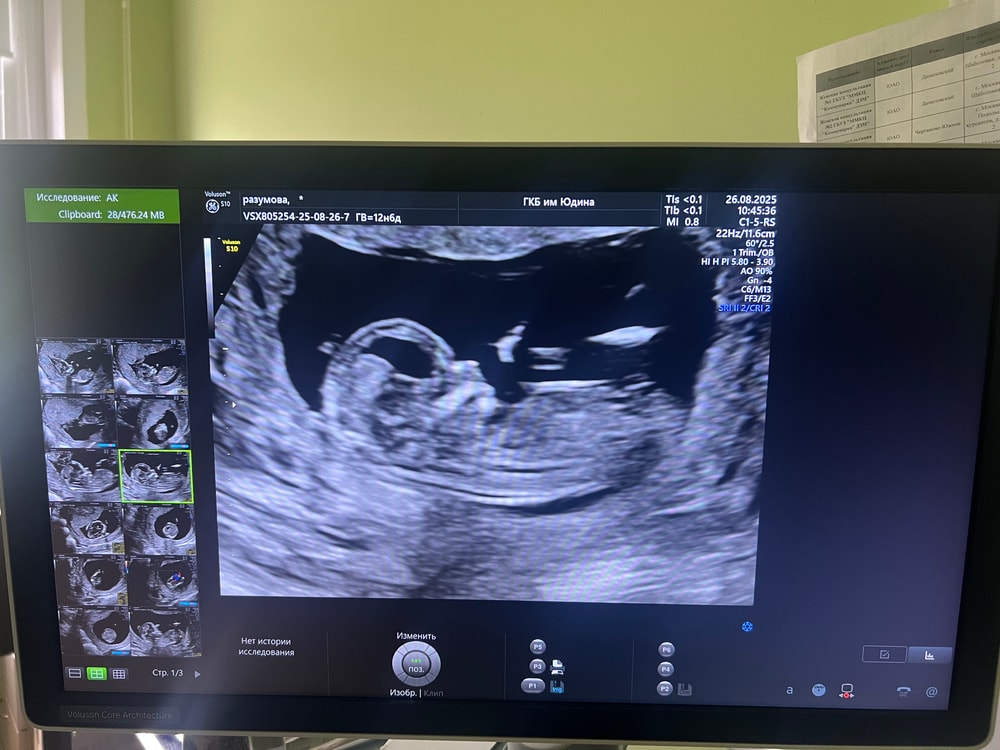

Сдала сегодня 1-й скрининг . 12 недель и 6 дней . По узи все супер . Я тут на фото бугорок разглядела . Нога это или признак мальчика не пойму . Посмотрите . И как думаете с какой недели пол будет точно виден на узи ? С дочкой только в 20 Нед увидели точно . Кровь сдавать не хочу на пол